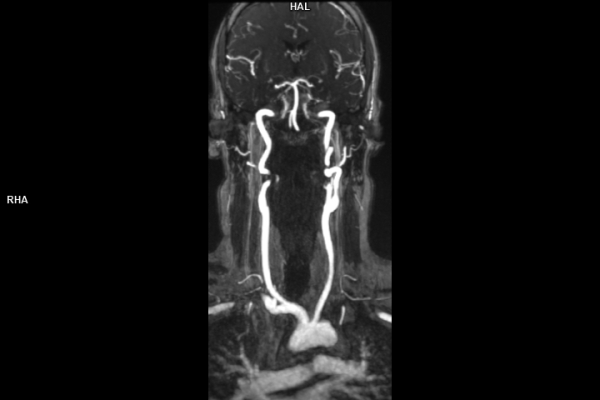

• Kardiovaskuläre Bildgebung (MRT- und CT-Untersuchungen des Herzen)

• Gefäßdiagnostik (CT-Angiographie)

Im Zentrum all meiner Bemühungen steht stets der Mensch. Mich motiviert am Beruf besonders die detektivische Spurensuche durch einen nicht-invasiven Blick in den menschlichen Körper. Radiologische Einschätzungen sind entscheidend für eine korrekte Diagnose und die Wahl der Therapie durch die behandelnden Ärzte.

Wir bieten ein breites Spektrum an Untersuchungen an, von Standarduntersuchungen der Gelenke, Organe oder großflächigen Körperregionen bis zu Spezialuntersuchungen zum Beispiel des Herzen oder der Gefäße. Zusätzlich werden Angiographien (Darstellung von Blutgefäßen), Endometriose-Abklärungen und Mamma-Untersuchungen durchgeführt. Genauere Details können Sie der MRT/CT-Übersicht und der Preisliste entnehmen, oder Sie wenden sich direkt an unser Team, das Sie gerne zur passenden Untersuchung berät.